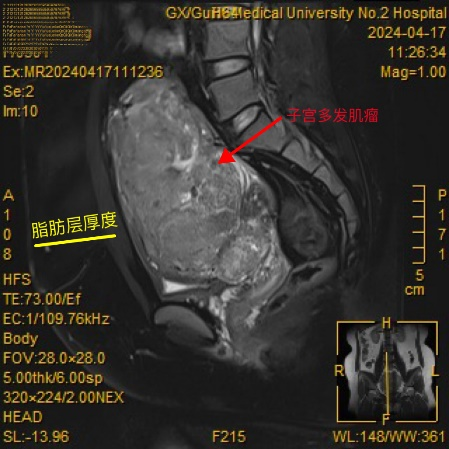

范女士,巨大子宫肌瘤反复复发10年余,在外院前前后后做了四次手术(两次开腹子宫肌瘤剥除术,两次腹腔镜下子宫肌瘤剥除术),2024年子宫肌瘤复发并出现月经紊乱、月经量增多,导致血色素只有54g/L的重度贫血,且身高仅147cm的她BIM指数竟高达35kg/m2,就诊多家医院均被婉拒,慕名转诊到桂林医学院第二附属医院。

因为多次手术和肥胖,手术难度极大,妇科联合胃肠外科、泌尿外科、麻醉医学科、放射影像科组成强大的MTD团队在纠正贫血后给予范女士再次的手术治疗。术中发现范女士盆腔及腹腔的粘连如术前所预料的一样非常严重,最终在MTD团队的共同努力下顺利完成了手术,患者康复出院。